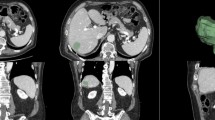

The patient cohort included a training set and an external validation set. The internal training set was formed by 51 patients (18 women and 33 men) with 61 years of median age (range 35–82 years) and 121 liver metastases. The validation cohort, from “Careggi Hospital”, Florence, Italy, was formed by 30 patients with single lesion (10 women and 20 men) and 60 years of median age (range 40–78 years). The patient characteristics are summarized in Table 1.

For each volume of interest (VOI), 851 radiomics features were extracted as median values using open-source PyRadiomics python package [58] and as reported previously in [76]. The extracted features are in compliance with feature definitions as described by the Imaging Biomarker Standardization Initiative (IBSI) [59] and as reported in [https://readthedocs.org/projects/pyradiomics/downloads/ Accessed on 21 December 2021]. Median values of radiomics features were considered for each segmented VOI.

In this study, we found that several metrics were statistically significant to characterize mucinous sub-type: 15 extracted from T2W SPACE; 13 from the arterial phase; 12 from the portal phase and 12 from the EOB-phase. The best results at univariate analysis were reached by the wavelet_LLH_glcm_JointEntropy extracted by T2W SPACE sequence with accuracy of 92%, a sensitivity of 83%, a specificity of 94%, a PPV and a NPV of 78 and 95%, respectively, with a cut-off value of 4.61. Also, linear regression model increased the performance obtained with a linear regression model of 15 significant features extracted by the T2W SPACE sequence with accuracy of 94%, a sensitivity of 92%, a specificity of 95%, a PPV and a NPV of 83 and 98%, respectively.